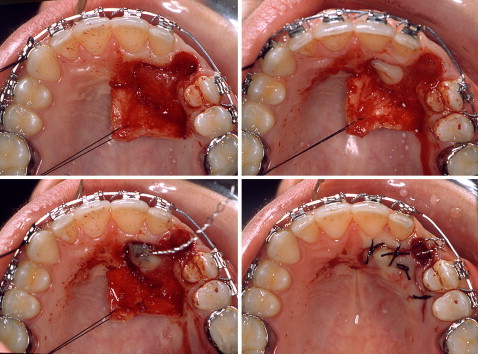

劉佳觀主任說,若阻生牙已造成相鄰牙齒往阻生牙區傾斜或移動,或合併對咬牙的增長,進而影響牙齒美觀及齒列排列,甚至造成咬合功能的干擾,則必須進一步治療,其治療計畫有三種方法,分別為拔除、自體移植或手術暴露合併矯正牽引。由於第三大臼齒阻生時,因牙弓長度不夠,大部分會選擇拔除,其他部位的阻生牙則以手術暴露合併矯正牽引為優先考量,優點為可以保留自己的牙齒,維持正常齒列與功能,缺點為治療時間長;若阻生牙的位置太深、方向屬於橫向阻生或牙齒彎曲角度過大,會建議拔除,優點為治療時間快,缺點為將來需裝假牙。若阻生牙的空間足夠且可完整的拔除,可考慮自體移植,優點為療程較短,缺點為牙齒要做根管治療,且可能產生與骨頭粘黏。

劉佳觀主任指出,若施以手術暴露合併矯正牽引的治療分成三階段:一、術前矯正:其目的是要提供足夠空間給阻生牙;二、手術暴露並黏著矯正器於牙冠;三、矯正牽引阻生牙至適當位置。手術暴露合併矯正牽引的治療的成功率高達九成五以上,一般而言,造成失敗的原因是牙齒本身與骨頭有粘黏,牙根嚴重吸收或牽引過程與鄰牙無法避開,而必須拔除;至於手術暴露合併矯正牽引依牙齒深度及方向等因素,治療時間平均為一至三年;劉佳觀主任呼籲民眾,如果發現牙齒生長有可疑情況,請立即就醫診治。